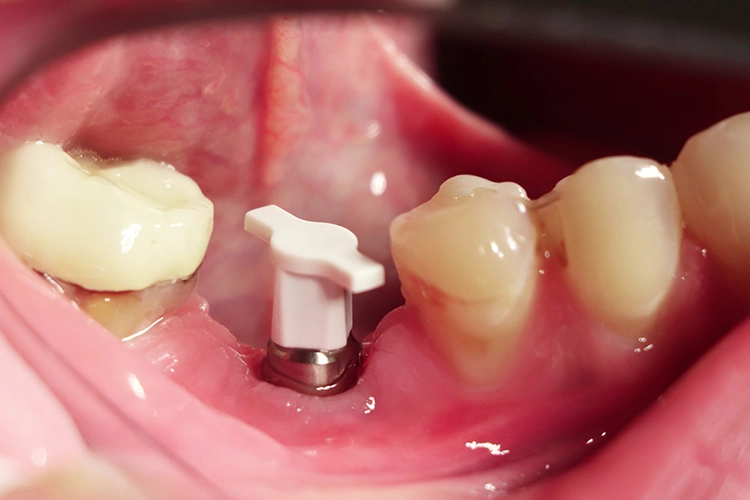

Im nächsten Schritt erfolgte die vollständig navigierte Implantation des Microcone-Implantates (Ø 5,0 mm, 9 mm Länge) in der Region 46 (Abb. 8-14) nach dem vom Hersteller empfohlenen Bohrprotokoll, das sich nach Knochenqualität und Implantatdurchmesser richtet. Die Chirurgie-Kassette (Abb. 6) ist übersichtlich aufgebaut und intuitiv zu bedienen. Zur schonenden Präparation des knöchernen Implantatbetts stehen je nach Implantatdurchmesser und Knochenqualität bis zu fünf verschiedene Bohrertypen mit Farbcodierung zur Verfügung. Das Implantat war für eine gedeckte Einheilung vorgesehen und der Kieferkamm wurde durch Nahtlegung speicheldicht verschlossen (Abb. 15).

Die Dokumentation des Implantatsitzes erfolgte mit einer postoperativen Panoramaschichtaufnahme (Abb. 16). Nach der gedeckten Einheilung erfolgte im Juni 2021 die geschlossene Implantatabformung mit Impregum. Abbildung 17 bis 25 zeigt den Ablauf von der Inzision drei Monate nach Implantation bis zum Einsetzen des Hybrid-Abutments mit Titan-Klebebasis und Zirkonaufbau bis zur finalen Zirkonkrone, die aufgrund einer Erkrankung der Patientin etwas später als vorgesehen im Juli 2021 eingegliedert werden konnte. Die Versorgung der insuffizienten Einzelkrone 47 erfolgt auf Patientenwunsch zu einem späteren Zeitpunkt.